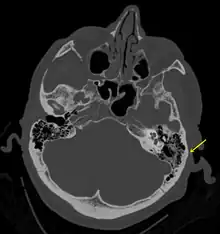

Temporal bone fractures

Acute injury to the internal carotid artery (carotid dissection, occlusion, pseudoaneurysm formation) may be asymptomatic or result in life-threatening bleeding. They are almost exclusively observed when the carotid canal is fractured, although only a minority of carotid canal fractures result in vascular injury. Involvement of the petrous segment of the carotid canal is associated with a relatively high incidence of carotid injury.[9]